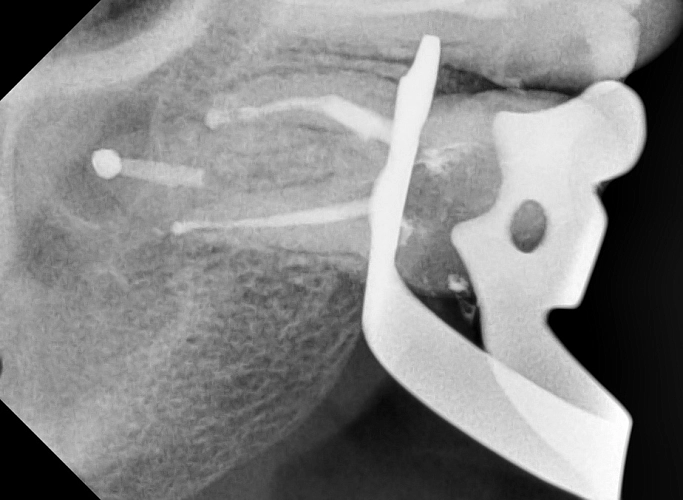

На следующих снимках видно, что отломок инструмента был успешно извлечён. Все каналы были пройдены, механически обработаны под микроскопом и запломбированы.

Работа врача -стоматолога -микроскописта Овчинниковой М.И